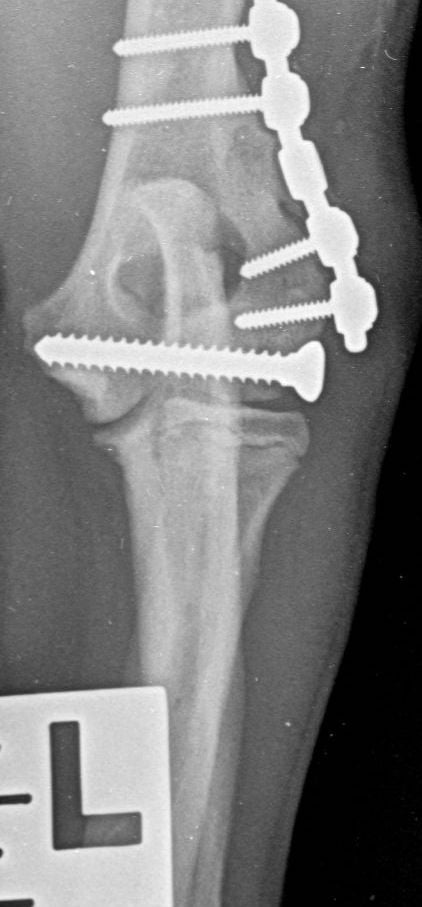

Only 29 dogs (30 fractures) returned for a follow-up examination at 31 to 60 days (median: 42 days), but all these fractures showed complete radiographic union (Figure 4). No minor complications were recorded in any of these patients. Four (13 percent) experienced a major complication: one was noted during the healing phase and three during the follow-up examination. All involved implant migration and all were successfully managed by implant removal or replacement. The short-term outcome was recorded as excellent in 23/30 fractures (77 percent) and good in 7/30 (23 percent).